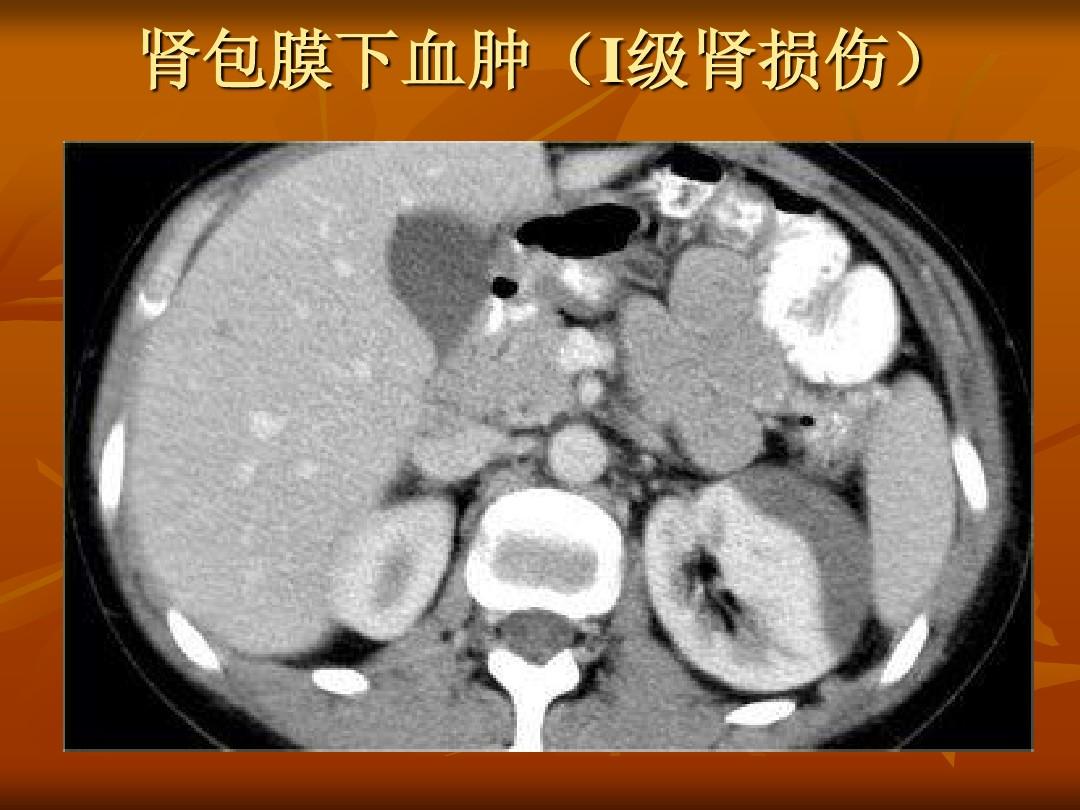

3、B超检查

腹部 b超检查在紧急情况下可以显示腹部器官的损伤,如腹腔积血等。

5、静脉肾盂造影检查

可显示骨盆的移位。肾脏造影提示肾损伤和腹膜后出血。